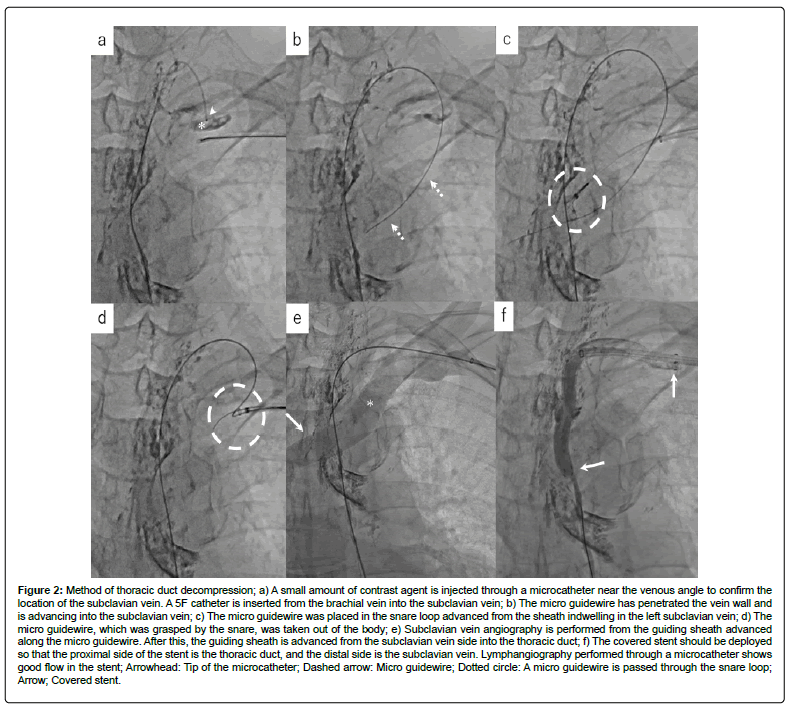

A microcatheter was inserted into the TD as before, and a 5F sheath was added to the left brachial vein. The TD pressure measured from the microcatheter was 109/99 mmHg (mean 103 mmHg), and that of the subclavian vein was 2/1 mmHg (mean 0 mmHg). Even in the resting state, the backflow of chylous fluid was confirmed through the microcatheter. We tried to approach the occluded Venous Angle (VA) from the TD side, but could not break through the occlusion again, and the guidewire penetrated the TD wall. Therefore, we planned to reinsert the guidewire into the subclavian vein by drilling it from outside of the vessel from the TD side (Figure 2). A microcatheter was advanced along the extravascular guidewire to the vicinity of the subclavian vein wall. It was confirmed with a small amount of iodine contrast agent that was injected through the microcatheter and distributed along the wall of the subclavian vein. We successfully penetrated the subclavian vein drilling with the guidewire and using the microcatheter as a backup. A 10 mm Amplatz GooseNeck Snare (ev3, Irvine, CA, USA) was inserted into the subclavian vein from a sheath. The guidewire was captured by this snare and pulled out of the sheath. We inserted a 6F guiding sheath (Destination, Terumo, Japan) into the TD using a through-and-through wire technique from the left brachial vein side. We deployed a 6 mm × 10 mm VIABAHN (W.L. Gore, Newark, DE) into the occluded TD by inserting it through the sheath. The stent-graft was dilated with a 5mm x 4cm balloon (Mustang, Boston, US), and TD-graphy showed good flow. Following treatment, the previously high TD pressure was decreased to 16/12 mmHg (mean 14 mmHg).

Figure 2: Method of thoracic duct decompression; a) A small amount of contrast agent is injected through a microcatheter near the venous angle to confirm the location of the subclavian vein. A 5F catheter is inserted from the brachial vein into the subclavian vein; b) The micro guidewire has penetrated the vein wall and is advancing into the subclavian vein; c) The micro guidewire was placed in the snare loop advanced from the sheath indwelling in the left subclavian vein; d) The micro guidewire, which was grasped by the snare, was taken out of the body; e) Subclavian vein angiography is performed from the guiding sheath advanced along the micro guidewire. After this, the guiding sheath is advanced from the subclavian vein side into the thoracic duct; f) The covered stent should be deployed so that the proximal side of the stent is the thoracic duct, and the distal side is the subclavian vein. Lymphangiography performed through a microcatheter shows good flow in the stent; Arrowhead: Tip of the microcatheter; Dashed arrow: Micro guidewire; Dotted circle: A micro guidewire is passed through the snare loop; Arrow; Covered stent.